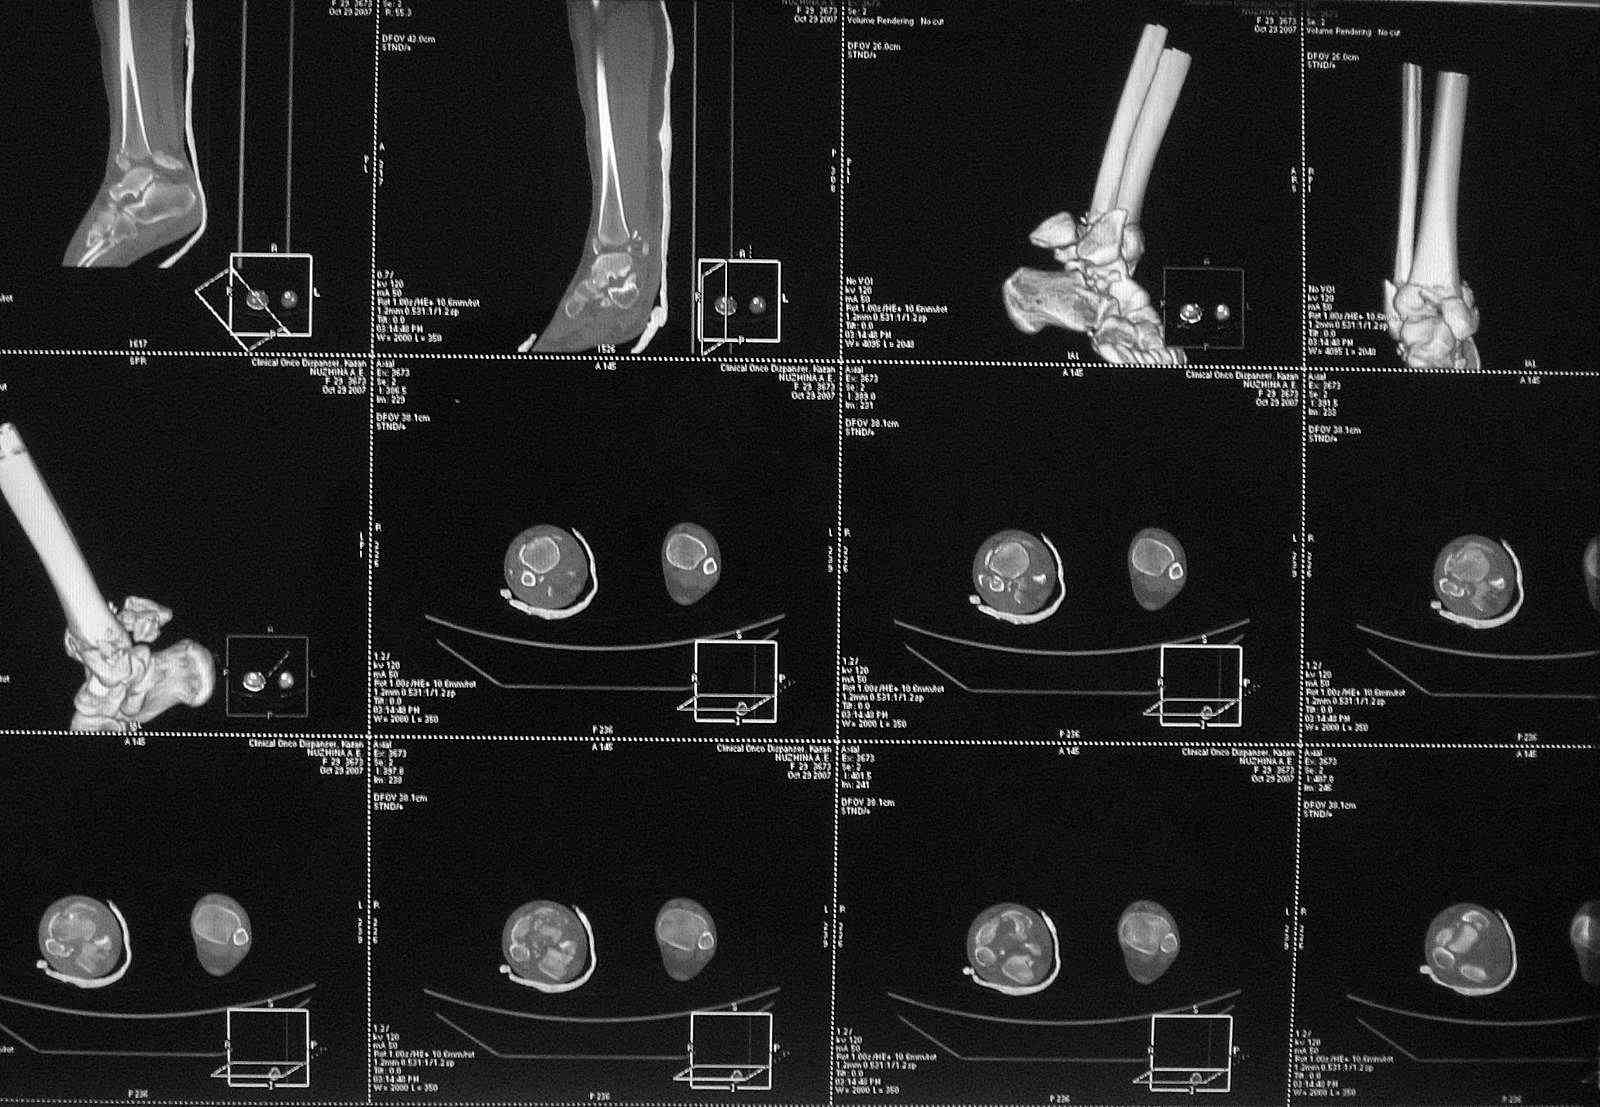

Добавлены КТ снимки. Прошу прощения за качество.

С уважением, Коваленко А.Н.